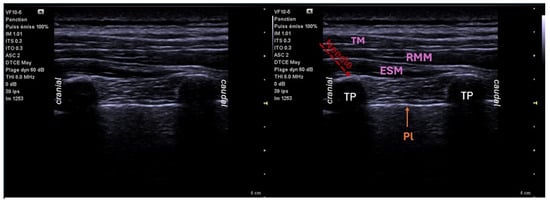

6.2. Erector Spinae Plane Block (ESPB)